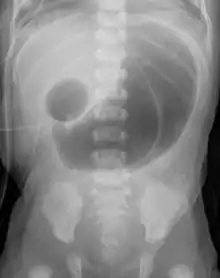

In radiology, the double bubble sign is a feature of pediatric imaging seen on radiographs or prenatal ultrasound in which two air filled bubbles are seen in the abdomen, representing two discontiguous loops of bowel in a proximal, or 'high,' small bowel obstruction. The finding is typically pathologic, and implies either duodenal atresia, duodenal web, annular pancreas, or on occasion midgut volvulus, a distinction that requires close clinical correlation and, in most cases, surgical intervention.[1][2][3]

Distal gas is more often seen with midgut volvulus, duodenal stenosis and duodenal web, though this not always present. In such cases, distinguishing the diagnoses depends on clinical presentation.[4]